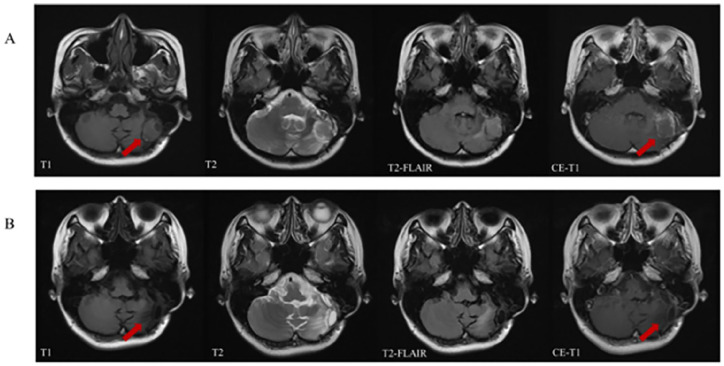

Case presentation: Here, we present a case of a middle-aged female with lung cancer BM, whose condition was assessed as progressive post-standard treatment including two local surgeries (both involving resection of cerebellar space-occupying lesions), stereotactic radiotherapy, chemotherapy and EGFR-TKIs. Subsequently, she underwent treatment with the traditional Chinese herbal formula gubenxiaoyi (GBXY). The patient was treated with GBXY for a total duration of 55 months. After treatment, a significant reduction of about 50% in intracranial lesions was observed, accompanied by an extension of both Intracranial Progression-Free Survival (IPFS) and Cognitive Deterioration-Free Survival (CDFS) exceeding 50 months.

Conclusion: These results demonstrate that in patients with lung cancer brain metastases (BM) unresponsive to standard treatments, GBXY not only has the potential to effectively prolong IPFS and decelerate cognitive decline, but may also contribute to a reduction in intracranial tumor burden. This suggests that GBXY could be a promising therapeutic option that warrants further investigation.